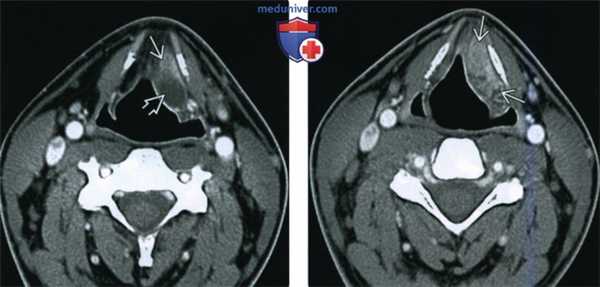

(Слева) При аксиальной КТ с КУ визуализируется смешанное вторичное ларингоцеле заполненное газом, со «стебельком», заполненным жидкостью. Ларингоцеле обусловлено обструкцией желудочка гортани опухолью (ПКР) ее преддверия, накапливающей контраст. Опухоль распространяется на ложную голосовую складку и обусловливает увеличение черпалонадгортанной складки.

(Справа) При корональной КТ с КУ у этого же пациента визуализируется наружное вторичное ларингоцеле, заполненное газом, вытянутый «мешок», заполненный жидкостью, а также опухоль (ПКР) преддверия гортани и собственно гортани. У всех взрослых пациентов с ларингоцеле, выявленном на КТ, необходимо исключить ПКР гортани.